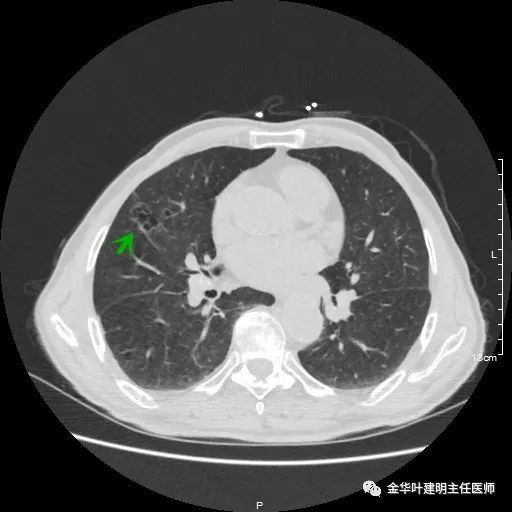

以上示右上病灶,我们称其病灶1。为囊腔型病灶,边缘为磨玻璃影,且轮廓清楚,局部有点状高密度,需考虑为囊腔型肺癌。单纯从单一病灶来看,这样的年纪可以随访或局部切除。